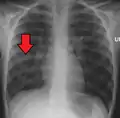

Chest X-ray of a pneumonia caused by influenza and Haemophilus influenzae, with patchy consolidations, mainly in the right upper lobe (arrow)